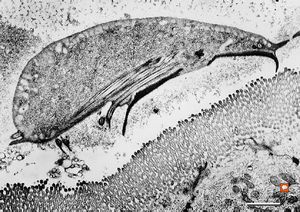

Giardia (lamblia) intestinalis